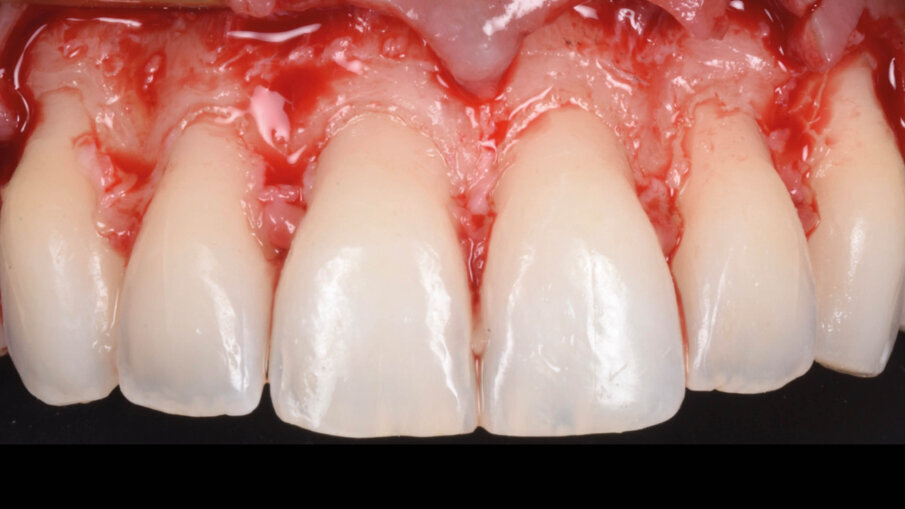

È perciò possibile durante la procedura di allungamento di corona clinica eseguire foto e video con un paziente completamente cooperativo. La prima procedura è la gengivectomia che ha lo scopo di eliminare la gengiva in eccesso e di esporre lo smalto dei denti altresì nascosto (Fig. 12). Una volta completata questa procedura si procede all’elevazione di un lembo a tutto spessore vestibolare che si estende per tutta la zona interessata dalla procedura. La mascherina chirurgica viene a questo punto ri-inserita in bocca per poter assistere la resezione della quantità di osso indicata per correggere la dimensione della zona di attacco sopra crestale (Fig. 13) La chirurgia ossea resettiva viene eseguita con l’ausilio di frese diamantate a palla con diverse dimensioni per le zone vestibolari e interprossimali oppure con strumenti piezo-elettrici. A procedura ultimata si può vedere come la nuova anatomia sia più consona all’attacco dei tessuti molli e favorente una miglior salute dell’attacco dento parodontale (Fig. 14).

Fig. 12_Esposizione dello smalto dopo la gengivectomia.

Fig. 14_Rimodellamento osseo dopo chirurgia resettiva.

La suture, in questo caso 5.0 riassorbibili (Flysorb mono, Butterfly, Cavenago Brianza, MI) hanno il solo scopo di mantenere i tessuti molli nella posizione corretta per agevolarne il riattacco e la guarigione, i nodi quando possibili vengono applicati sul versante palatale (Fig. 15). A novanta giorni dalla chirurgia si può apprezzare l’ottima guarigione e maturazione dei tessuti e come l’interfaccia dente gengiva sia migliorata sia all’esame intra che extra-orale (Fig. 16). Le foto intra ed extra-orali fatte a 24 mesi dall’intervento testimoniano l’ottimo risultato ottenuto e la sua stabilità (Fig. 17).